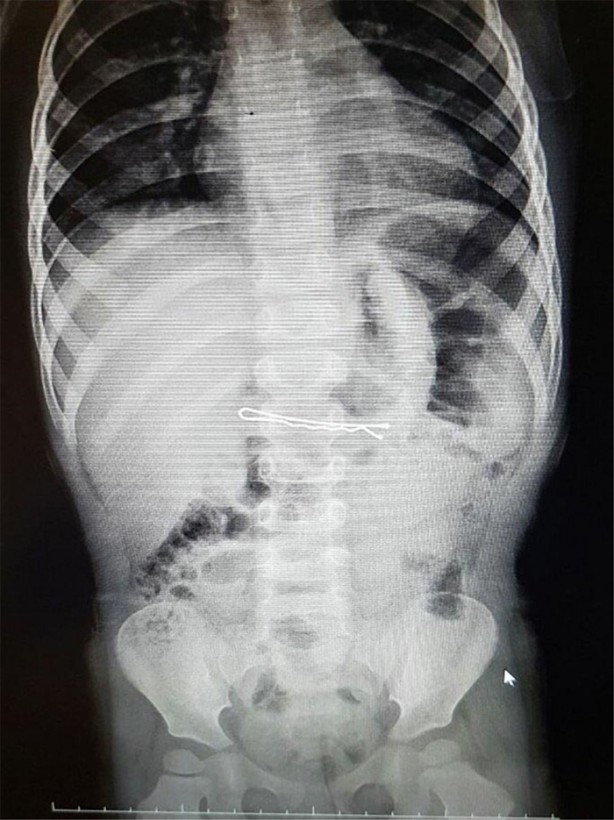

İzmir Tepecik Eğitim ve Araştırma Hastanesi Çocuk Gastroenteroloji Bölümü'nün, yabancı cisim yutan çocukların nefes ve borusu ile midelerinden çıkarttığı, anahtarlık, madeni para, saat pili, ataç, çengelli iğne ve çivi gibi objeler görenleri hayrete düşürdü.

Bu objelerden en tehlikelisinin piller olduğuna dikkat çeken Doç.Dr. Maşallah Baran, "Piller kimyasal mekanizmayla mukozayı yakıyor, özellikle yemek borusu çok duyarlı pillere, hele ki yeni takılmış bir pilse saatler içinde şahit olduğum bir kaç vaka var, yemek borusunu kömür haline getirebiliyor" dedi.